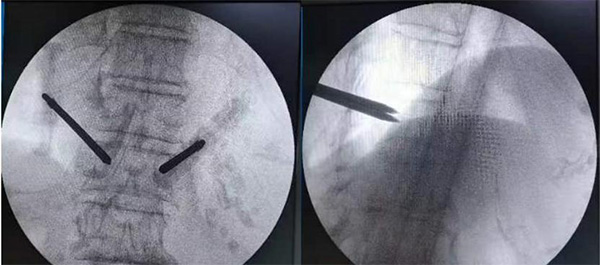

图为术中双侧穿刺